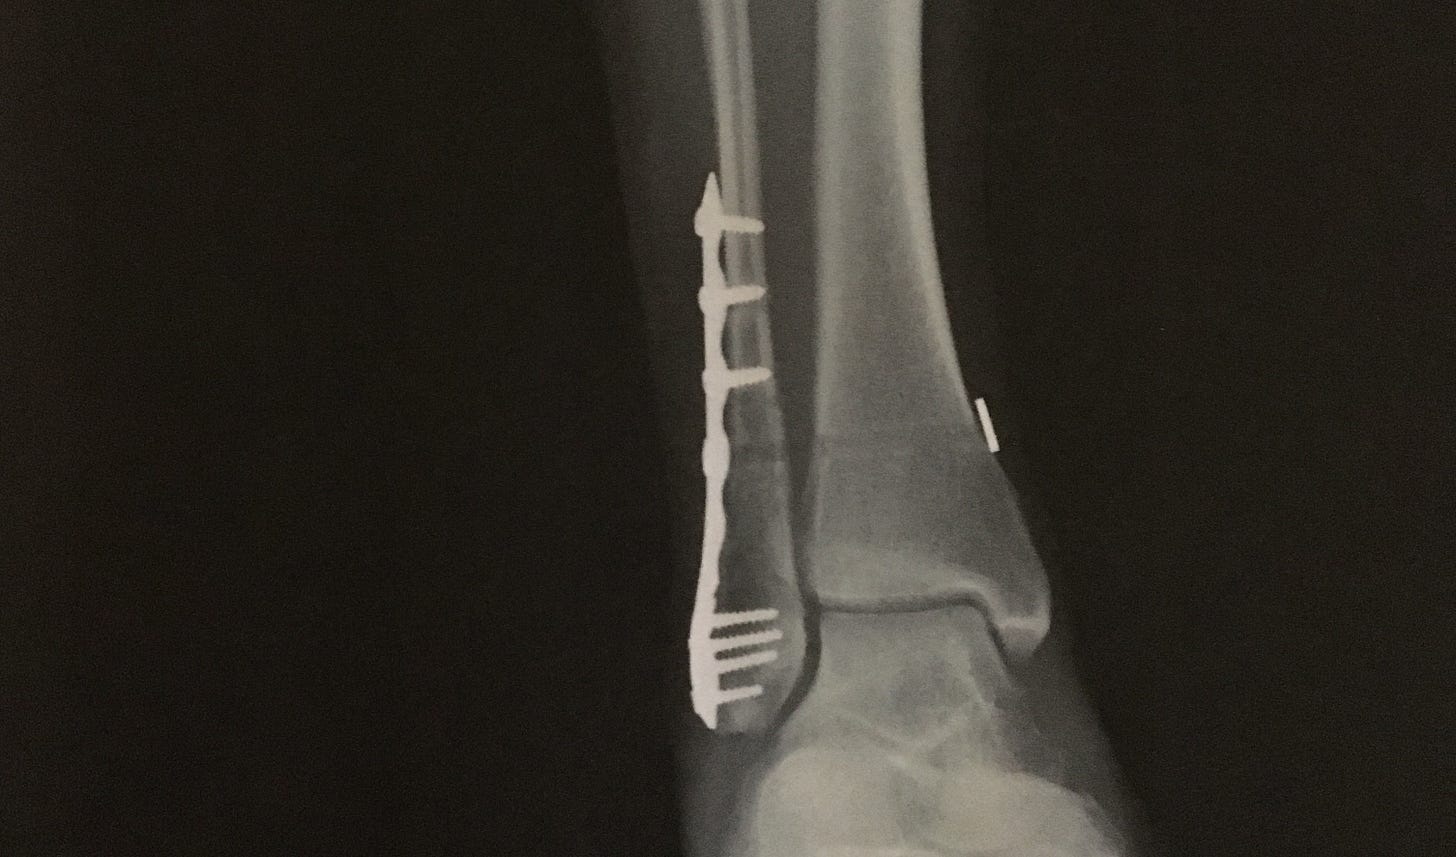

Once I was past the acute post-surgery pain, I have mostly been taking ibuprofen and Tylenol with the occasional stronger medication at night to sleep. As I take less and less, I'm feeling more and more aches in my whole body, and I know it's from being sedentary and stuck in weird positions all the time. Or, again, age. My shoulders. My back. My neck. My collar bones? I'm ready to spend more time moving around, and while I'm still non-weight-bearing, that means whatever I can do on the floor in my back room. More core, more stretching, more pull ups. I'm looking forward to physical therapy. I have been stretching my ankle every day, and it's getting less and less stiff, which I was pretty dubious would ever loosen up. When the surgeon flexed my foot right out of the splint last week, I thought my Achilles was going to snap. But he was just showing me how painful the healing process was going to be so that I wouldn't be alarmed by it. Now, I can't wait to start putting weight on it in a couple of weeks however much it will hurt.

I'm most eager for the return of my calf muscle. It's disturbing to look down at my leg and not recognize it as my own. It looks nothing like my other, "good" leg anymore. And it has begun to shed its skin, to molt, like it's becoming something new. Sheets of skin have begun falling off of it. And that's nothing to what is happening around the surgical incision. That's its own mess. I'm trying to love it anyway. Our healing bodies can look ugly, but the process is nonetheless miraculous. Sometimes when I'm laying still at night, it seems like I can feel my bones knitting themselves back together again. Or tendons, ligaments. Nerves. It feels like fire, or electricity, flaring up my shin.